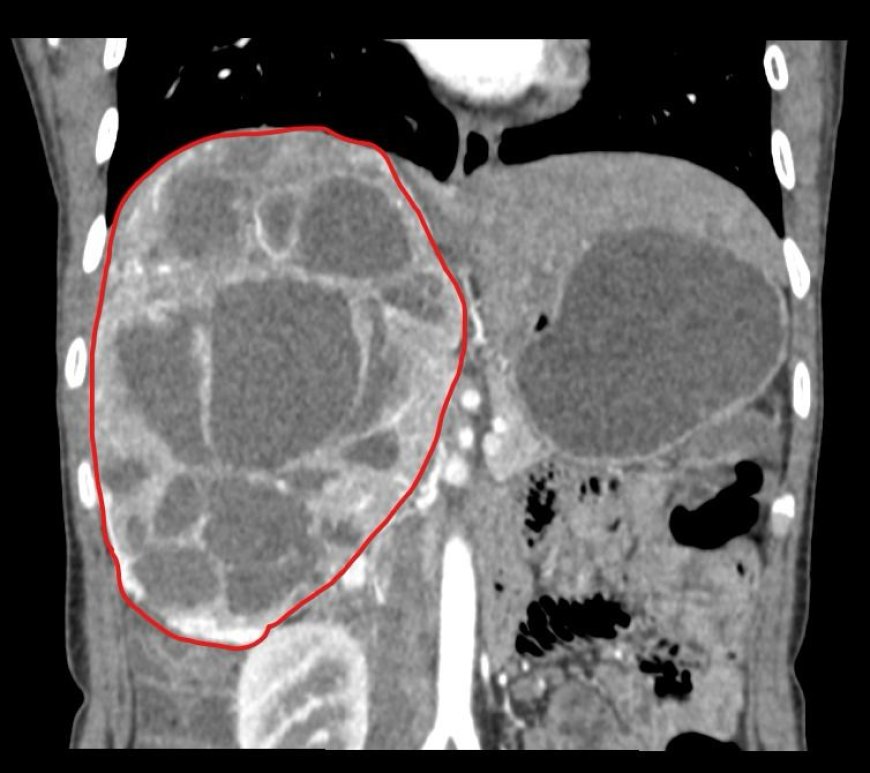

यह ट्यूमर दाहिनी एड्रिनल ग्रंथि से उत्पन्न हुआ था। रोगी को लंबे समय से अनियंत्रित रक्तचाप, अत्यधिक पसीना आने और दिल की धड़कनों में तेजी की शिकायत थी — जो फिओक्रोमोसाइटोमा की प्रमुख लक्षण होते हैं। यह एक दुर्लभ लेकिन गंभीर स्थिति होती है जिसमें शरीर में अत्यधिक कैटेकोलामाइन हार्मोन बनते हैं।

सीटी स्कैन और थ्रेड वेस्कुलर रिकंस्ट्रक्शन से पता चला कि यह ट्यूमर अत्यधिक रक्तसंचारित था और IVC (इंफीरियर वेना केवा), यकृत, दाहिनी वृक्क शिरा, डायाफ्राम और ड्योडेनम जैसे महत्वपूर्ण अंगों के अत्यंत समीप था, जिससे शल्य चिकित्सा अत्यंत जटिल बन गई।